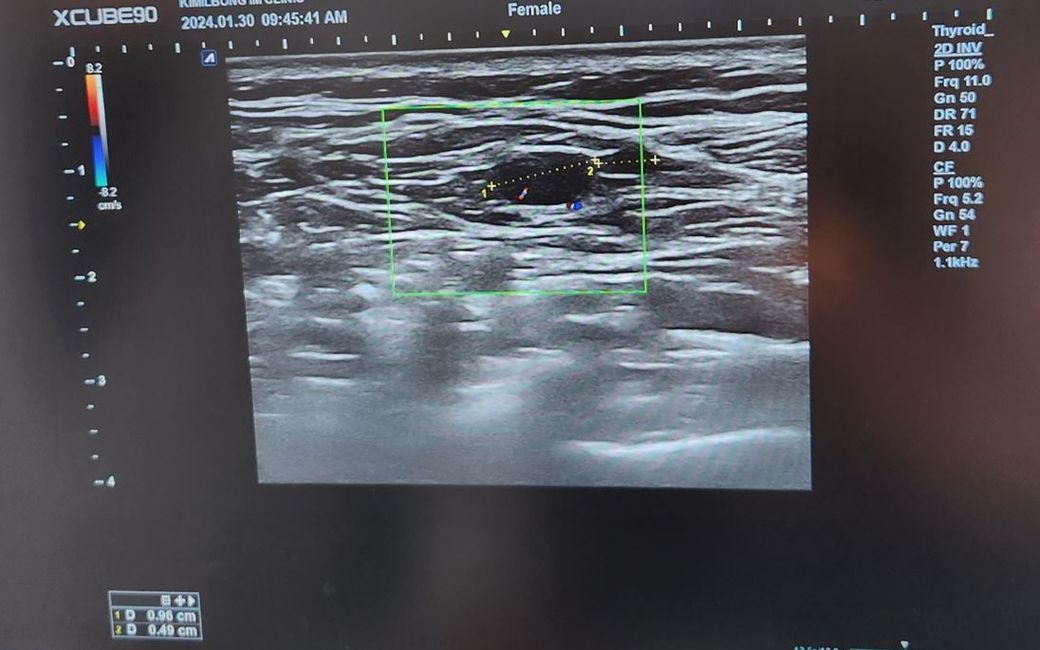

초음파 사진 한번 봐주세요 ㅠ정상 임파선일까요?

왼쪽 쇄골위에 멍울 혹이 만져져서 병원가서 초음파를 오늘 다시했습니다 ㅜ

외과, 내과 2군데모두 임파선이라고 하시는데

1. 정상 임파선 모양일까요?

2. 원래 임파선안에는 저렇게 혈류가 흐르는게 정상일까요? ㅠ

• 1번 째 사진

단편적인 사진 한 장으로 말씀드리긴 어려우나 임파선 비대의 가능성이 생각됩니다.

보여주신 사진 하나만으로 판단할 수 없지만 정상림프절 가능성이 높아보이긴 합니다.